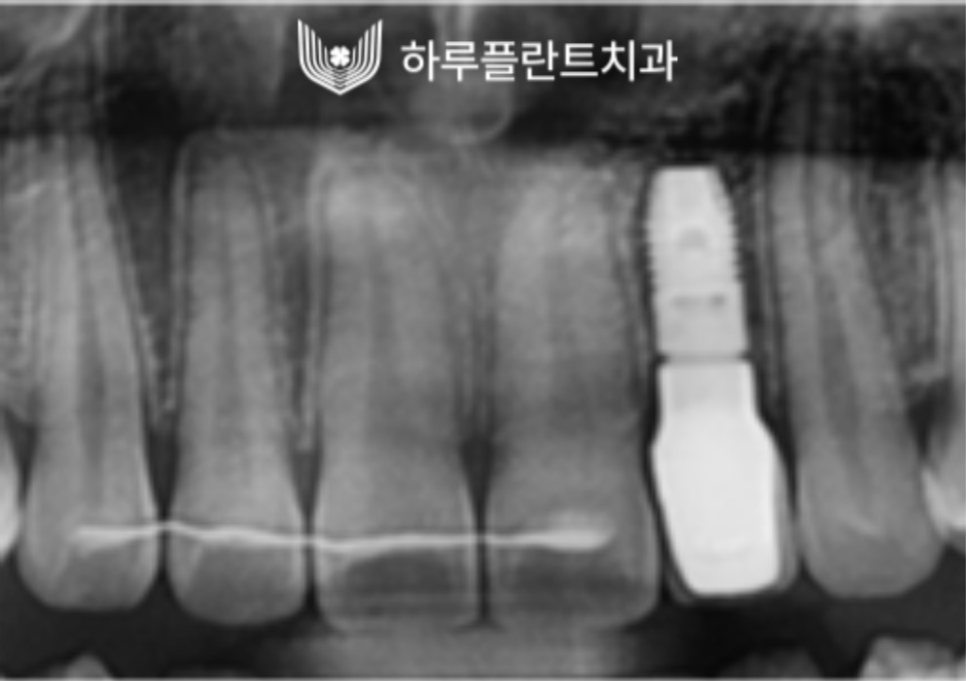

(왼) 뼈이식을 동반한 임플란트 식립 X-ray 사진입니다. / (오) 최종 구강 내 X-ray 사진입니다.

안정적으로 정확한 방향으로 식립된

모습을 확인할 수 있으며

이렇게 잘 식립된 임플란트는

사후관리만 꼼꼼히 잘 이루어진다면

반영구적으로 사용할 수 있습니다.